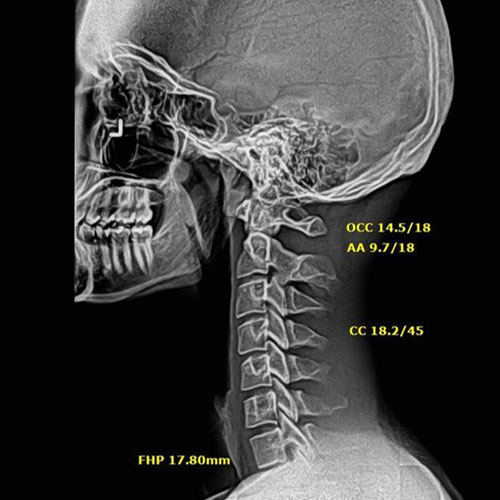

In this case, initial cervical spine X-rays revealed a significant loss of normal neck curvature, a condition that places excessive strain on the spine and nervous system. When the cervical curve is reduced, the head shifts forward, increasing stress on spinal joints, discs, and nerves — often leading to chronic neck pain, headaches, migraines, and neurological symptoms.

Before Chiropractic Treatment: The patient’s X-rays showed a flattened cervical curve, meaning the neck was no longer supporting the head in its ideal position. This type of misalignment is commonly linked to long-term spinal degeneration, nerve irritation, and persistent symptoms that don’t resolve with medication alone.